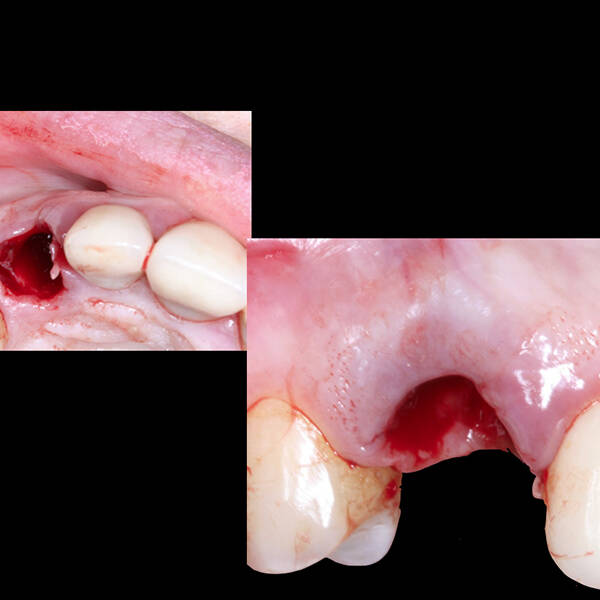

- Cirurgia de Instalação dos Implantes: Os implantes são fixados no osso maxilar ou mandibular, proporcionando uma base sólida para a prótese.

- Ausência de infecções ou doenças periodontais ativas.